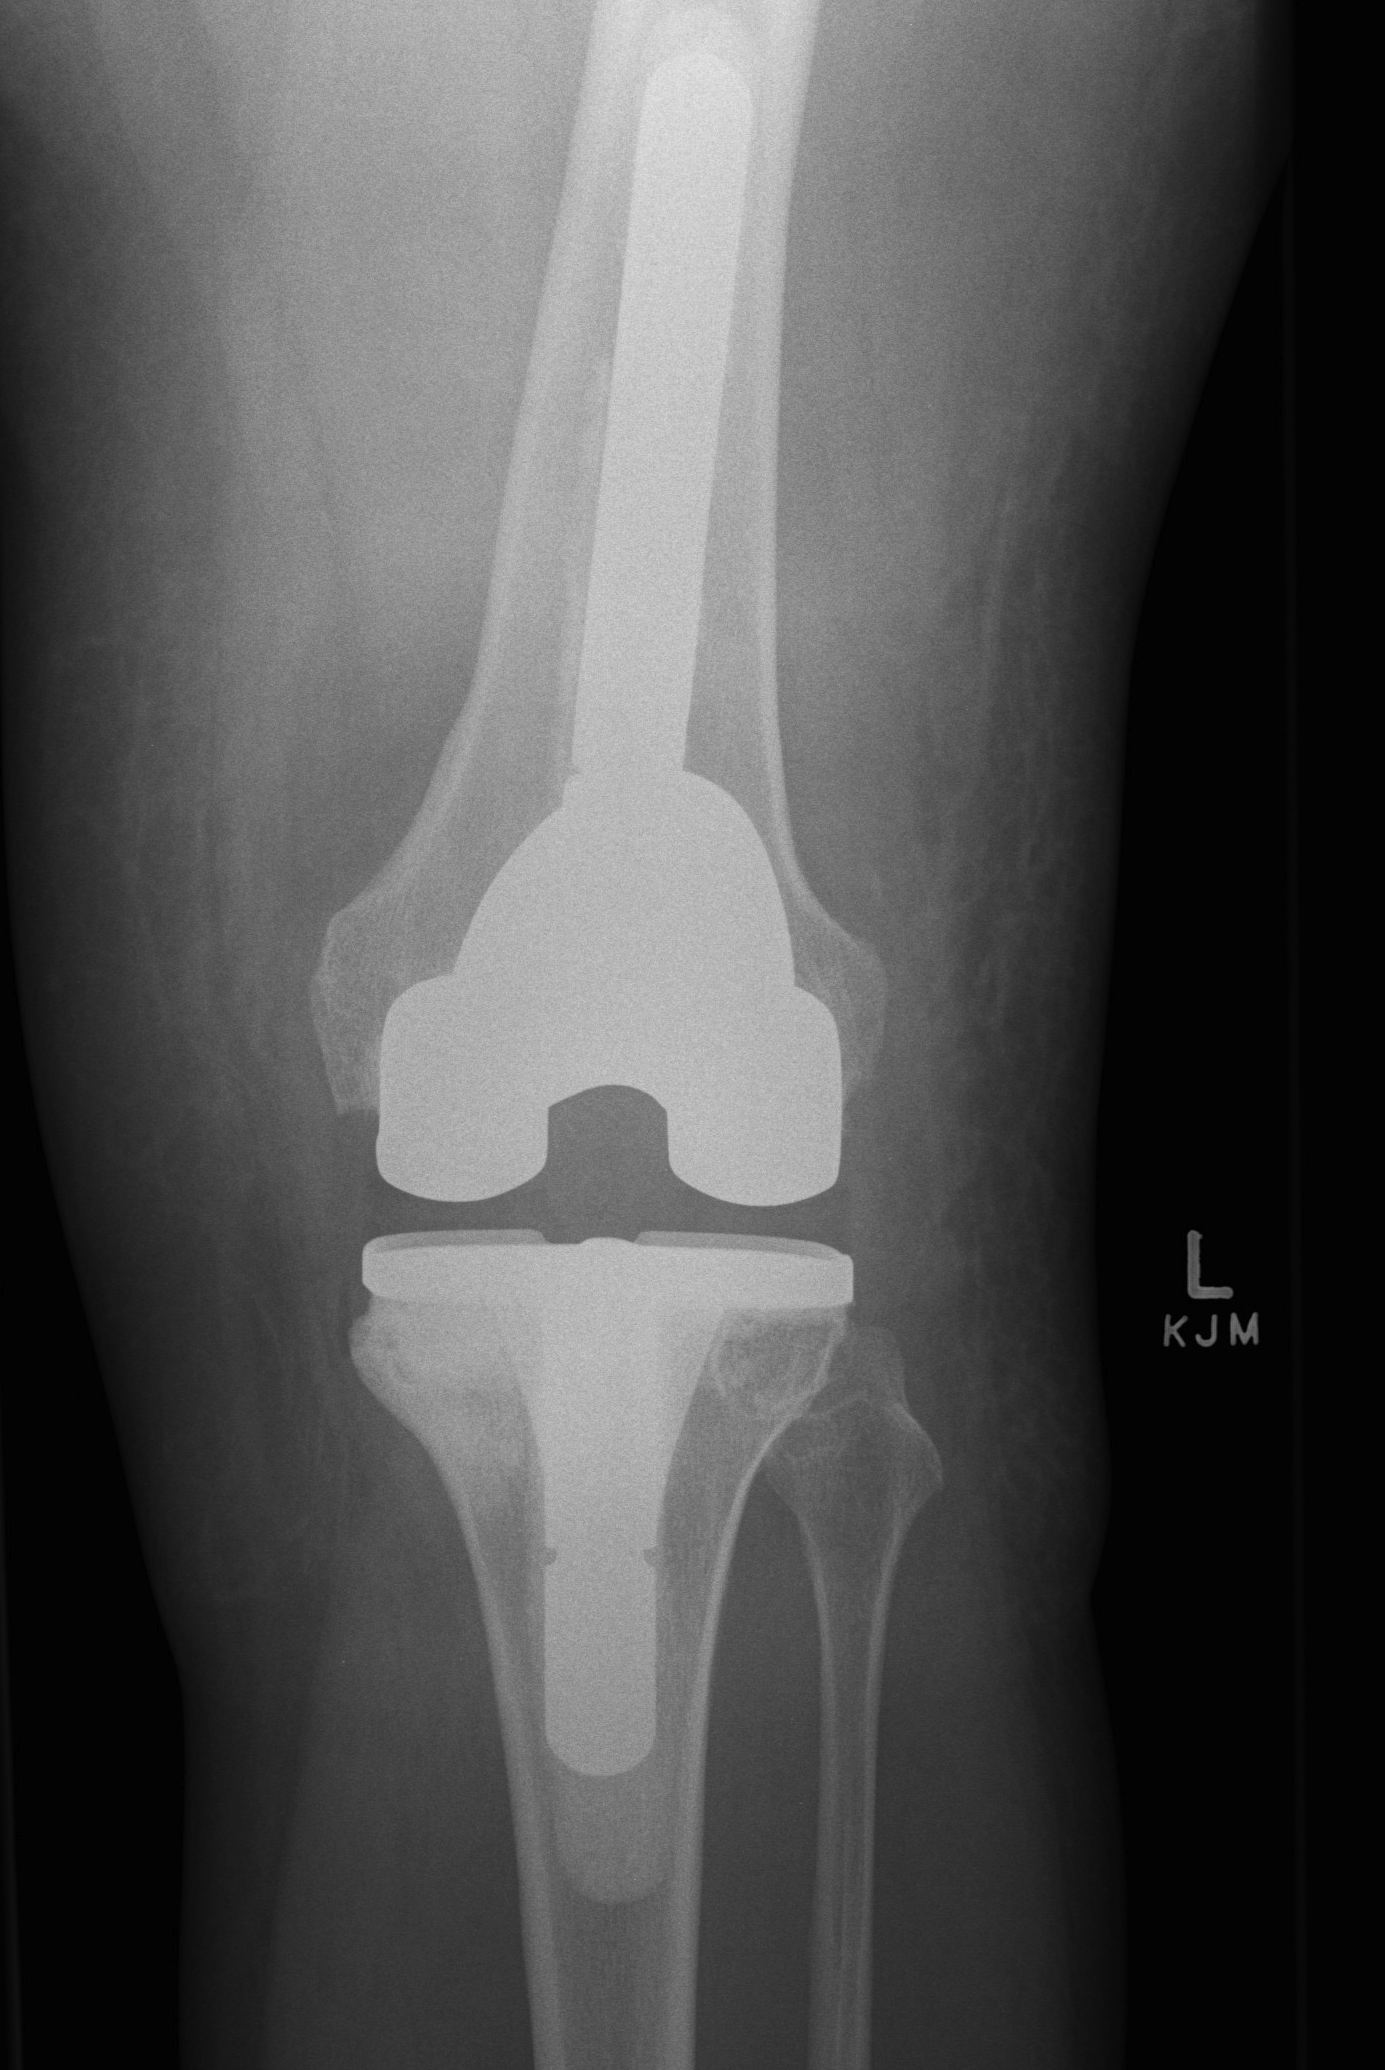

Patient 2